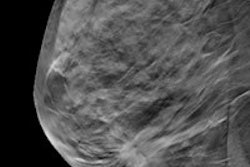

For the study, Castells and colleagues analyzed data from more than 500,000 women between the ages of 50 and 69 who underwent screening mammography at least once between 1994 and 2010. Of the total cohort, 76,075 women had false-positive exams, which the researchers defined as any screening mammogram with a BI-RADS score of 3, 4, 5, or 0 (thus requiring further diagnostic tests) (Radiology, February 15, 2016).

Compared to women with negative mammograms, those with false-positive results had a higher overall risk ratio of cancer, as well as a higher risk of screen-detected and interval cancers, the researchers found. The risk increased in women who had calcifications -- whether those calcifications were or were not associated with masses.